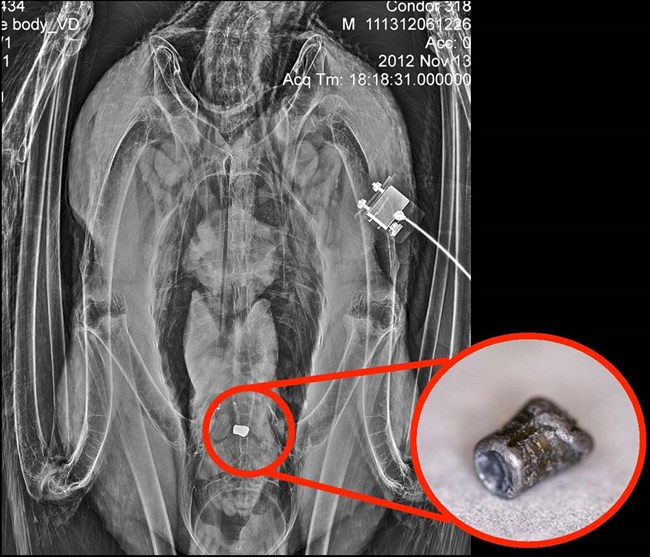

A radiograph image shows the digestive tract of a condor. A large white object on the radiograph is circled in red, and a pullout photo shows a closer image of what it is - a lead bullet fragment that the condor ate.

This is a radiograph of a condor that consumed lead ammunition; you can see one large fragment and a few smaller pieces of lead above it. The pullout photo is the actual fragment that was removed from the bird.